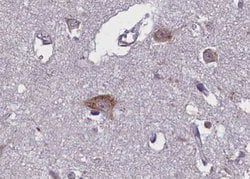

| Immunohistochemistry (Paraffin), Western Blot, Immunocytochemistry | |

Invitrogen™ Phospho-TRKB (Tyr706) Polyclonal Antibody

Antibody detects endogenous levels of Trk B only when phosphorylated at Tyrosine 706.